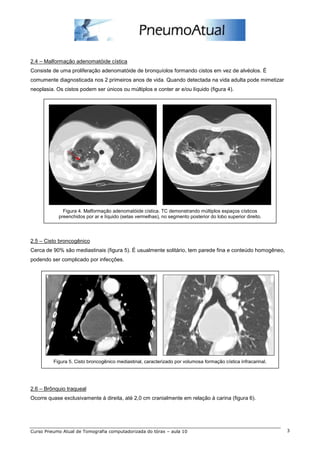

4.2 – Seqüestro broncopulmonar

Representa uma anomalia da ramificação traqueobrônquica com retenção do suprimento arterial sistêmico

embrionário. Esta é a teoria mais aceita, embora alguns autores postulem a origem adquirida. No seqüestro

intralobar (figura 10), o suprimento sistêmico costuma vir de um ramo da aorta, de vasos do abdome

superior e mesmo de artérias coronárias, sem colaboração da artéria pulmonar. A drenagem é feita por

veias pulmonares. Os sítios mais comuns são os lobos inferiores (60% à esquerda; 40% à direita). O

pulmão adjacente apresenta hiperinsuflação localizada (mais provavelmente representando aprisionamento

aéreo).

Figura 10. Seqüestro pulmonar intralobar. TC após injeção venosa de meio de contraste evidenciando

consolidação no lobo inferior esquerdo (seta vermelha) suprida por duas artérias sistêmicas (seta verde)

originadas da aorta descendente.

4.3 – Seqüestro extralobar

É muito menos freqüente (1:6), mais comum no sexo masculino (80%) e tem seu próprio revestimento

pleural, sendo mais comum à esquerda junto ao diafragma. O suprimento arterial é a partir de pequenas

artérias originadas da aorta, mas pode haver suprimento pela artéria pulmonar; a drenagem venosa se faz

para veias sistêmicas (ázigos e hemiázigos). Seus brônquios podem se conectar com o trato digestivo.